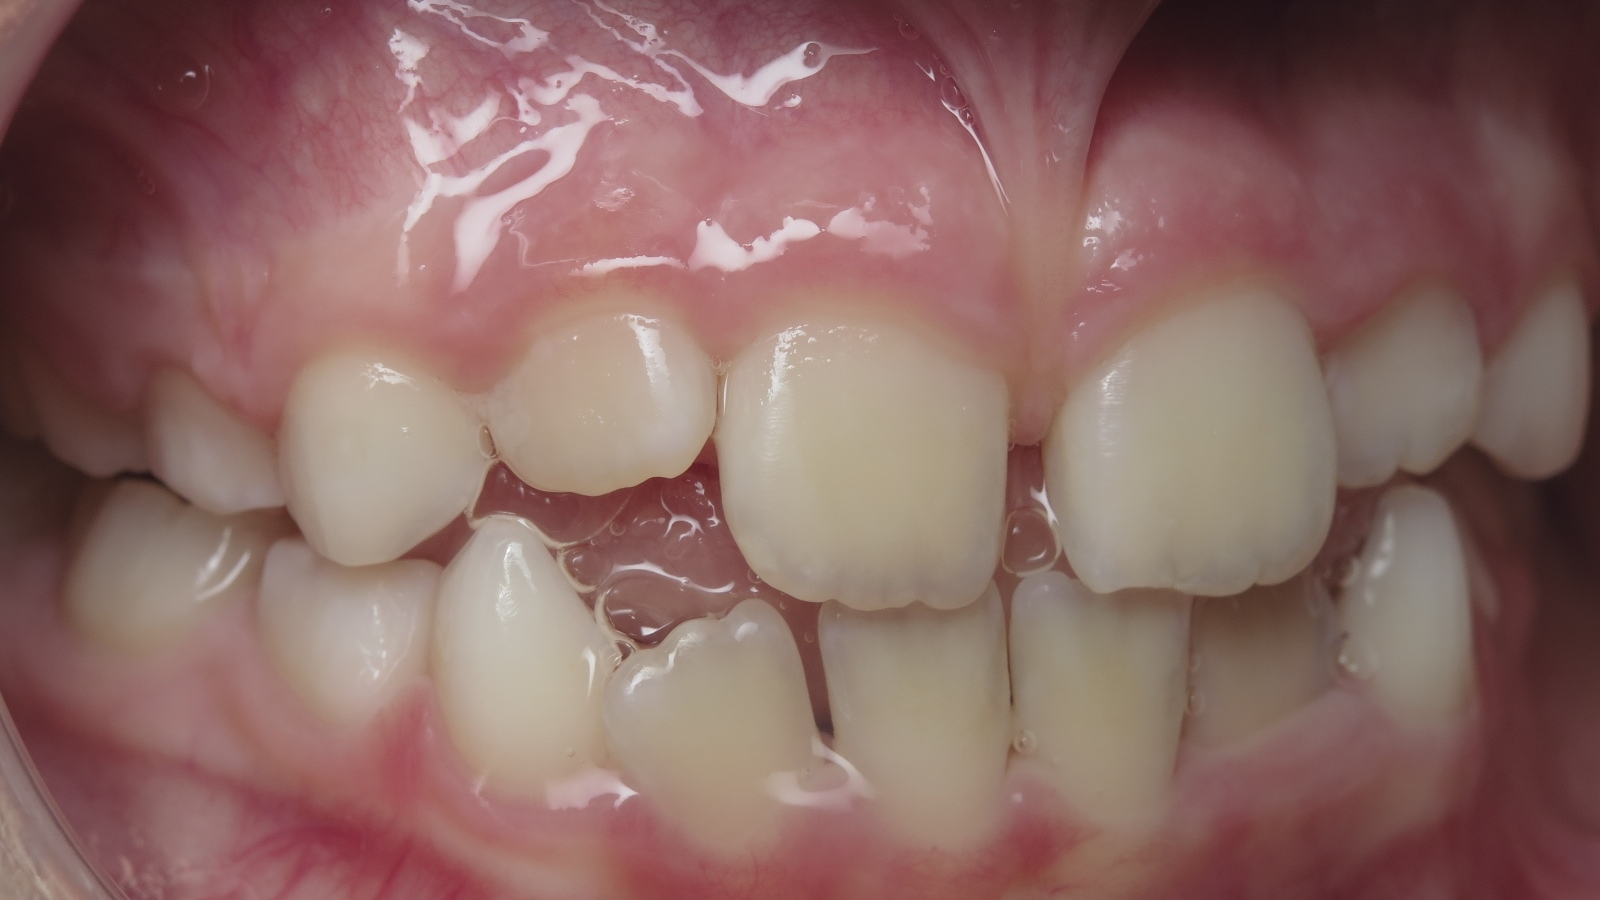

surveillance évolution de la dentition

bilan de début et en cours de traitement